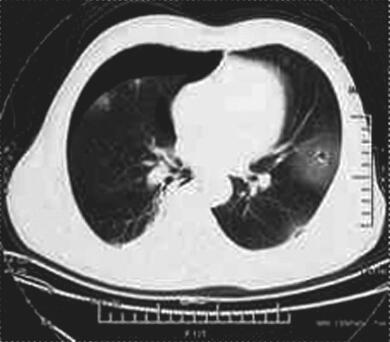

图3 2014年12月21日胸部CT

左舌段空腔病灶较前增大,左下叶基底段出现疑似空洞病灶,病灶周边可见斑片影,双侧气胸,以右侧为主